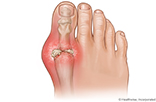

La gota es un tipo de artritis. Puede causar un ataque repentino de dolor ardiente, rigidez e hinchazón en una articulación que suele ser la del dedo gordo del pie. Estos ataques pueden suceder una y otra vez a menos que se trate la gota. Con el tiempo, pueden dañar articulaciones, tendones y otros tejidos. La gota es más común en hombres.

La señal más común de la gota es un ataque nocturno de hinchazón, sensibilidad, enrojecimiento y dolor agudo en el dedo gordo del pie. También puede tener ataques de gota en el pie, el tobillo o las rodillas u otras articulaciones. Los ataques pueden durar unos pocos días o varias semanas antes de que el dolor desaparezca. Es posible que no ocurra otro ataque por meses o años.

• Calor, dolor, hinchazón y sensibilidad extrema en una articulación, generalmente la articulación del dedo gordo del pie. Este síntoma se llama podagra. El dolor suele empezar durante la noche. Puede empeorar rápidamente, durar horas y ser tan intenso que hasta la menor presión de una sábana es intolerable.

• Piel muy enrojecida o amoratada alrededor de la articulación afectada. La articulación puede parecer infectada.

La gota suele presentarse después de varios años de acumulación de cristales de ácido úrico en las articulaciones y tejidos que las rodean. Un ataque de gota suele comenzar durante la noche con un dolor moderado que empeora. Un ataque de gota generalmente causa dolor, hinchazón, enrojecimiento y calor (inflamación) en una sola articulación, la mayoría de las veces en el dedo gordo del pie. Luego, los síntomas desaparecen gradualmente.